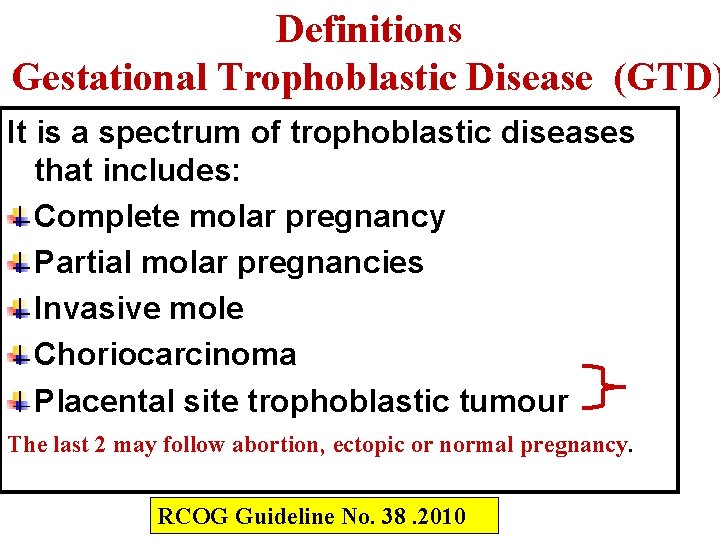

Definitions Gestational Trophoblastic Disease (GTD) It is a spectrum of trophoblastic diseases that includes: Complete molar pregnancy Partial molar pregnancies Invasive mole Choriocarcinoma Placental site trophoblastic tumour The last 2 may follow abortion, ectopic or normal pregnancy. RCOG Guideline No. 38. 2010